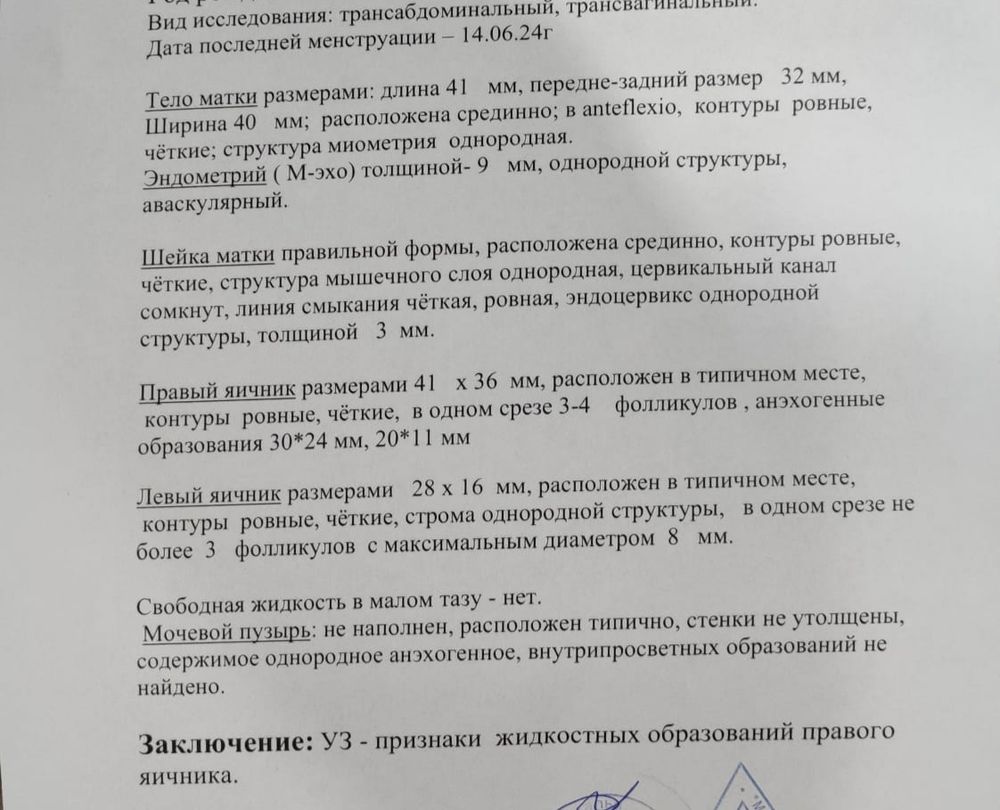

Сегодня сделала овитрель, как думаете есть шанс на беременность? Пью прогинову и через 2-3 дня добавляю Дюфастон

Сегодня сделала овитрель, как думаете есть шанс на беременность? Пью прогинову и через 2-3 дня добавляю Дюфастон